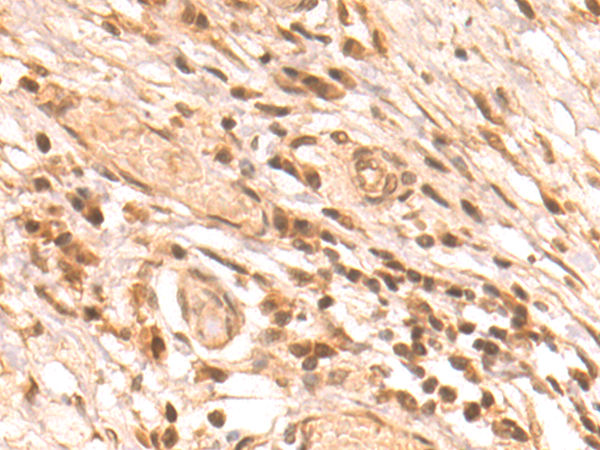

分类: 科研抗体货号: P11181别名: AMD; SAMDC; ADOMETDC应用: IHC反应种属: Human, Mouse, Rat